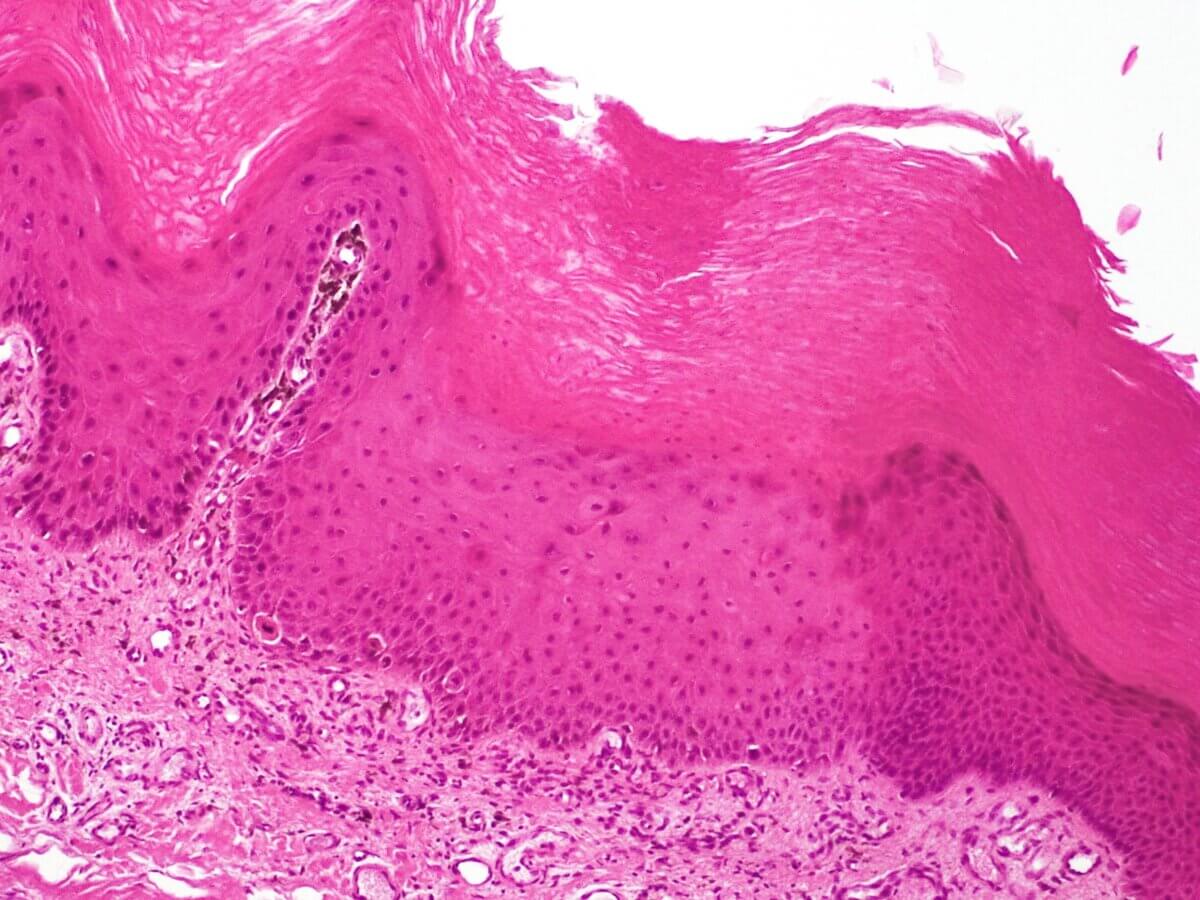

Ein Akanthom ist eine benigne Geschwulst, die von der Stachelzellschicht der Epidermis ausgeht.